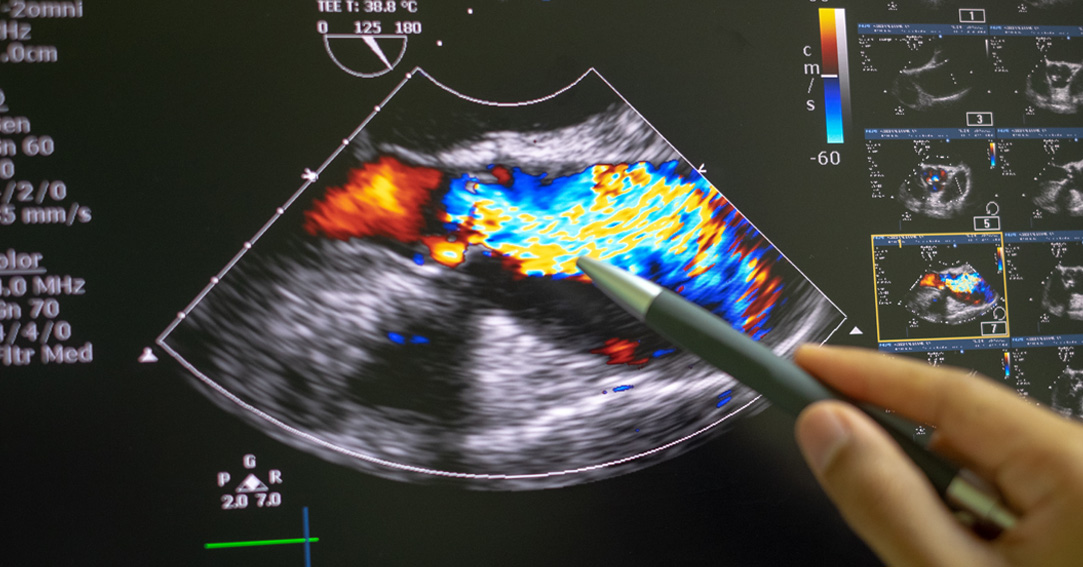

Aortic stenosis is a narrowing of the opening controlled by the heart’s aortic valve, which helps move oxygenated blood out of the heart and toward the body. The smaller opening reduces the amount of blood able to leave the heart, resulting in decreased oxygen delivery to the body and an increased blood pressure in the heart. If left untreated, aortic stenosis can lead to heart failure.

“The cause of aortic stenosis is a progressive thickening and hardening, or calcification, of the aortic valve, which restricts its ability to fully open,” said interventional cardiologist M. Fuad Jan, MD, Advocate Aurora Research Institute’s principal investigator for the study. “Right now, the only treatment is aortic valve replacement through surgery. There is currently no way to slow down aortic valve calcification, which is why the possibility of a potential drug treatment is so exciting.”